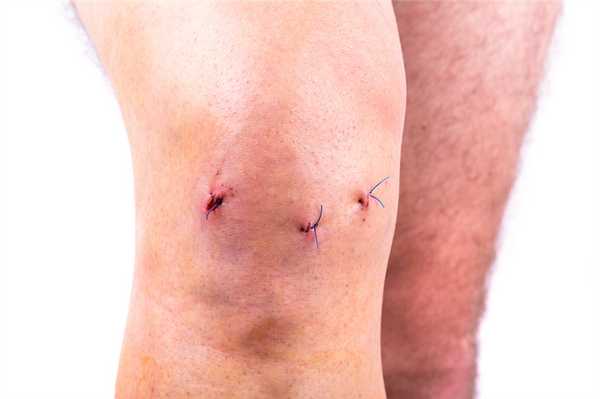

По окончании хирургии операционное поле промывается, а весь инструментарий извлекается. Доктор производит обработку дезинфицирующими составами рану, ставит дренаж и делает маленький шов, который закрывает стерильным лейкопластырем. На прооперированное колено, чтобы придать ему максимальную обездвиженность, накладывается плотная фиксирующая повязка от стопы до середины бедра.

- На асептическую обработку и перевязки пациенту нужно являться к врачу каждые два дня на протяжении 7-12 суток. Возможно, если в суставе будет выявлено скопление выпота, в момент контрольных посещений сделают его эвакуацию при помощи пункции. Швы снимаются не ранее чем по истечении недели.